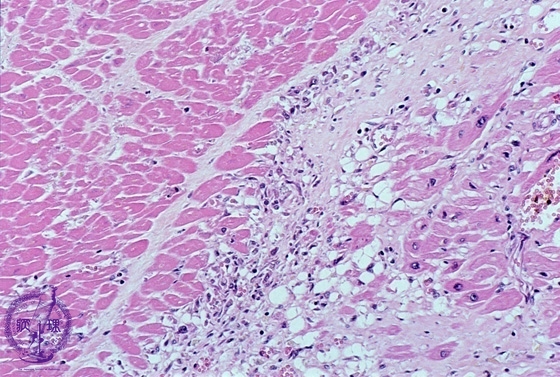

- 3.Cardiovascular system

- ★(2)Myocardial infarction (acute)

Microscopic image (HE, low power): Healing infarct at 3 weeks. The infarcted area comprises necrotic myocytes with karyorrhectic debris, capillary and fibroblastic proliferation and a lymphohistiocytic infiltrate.